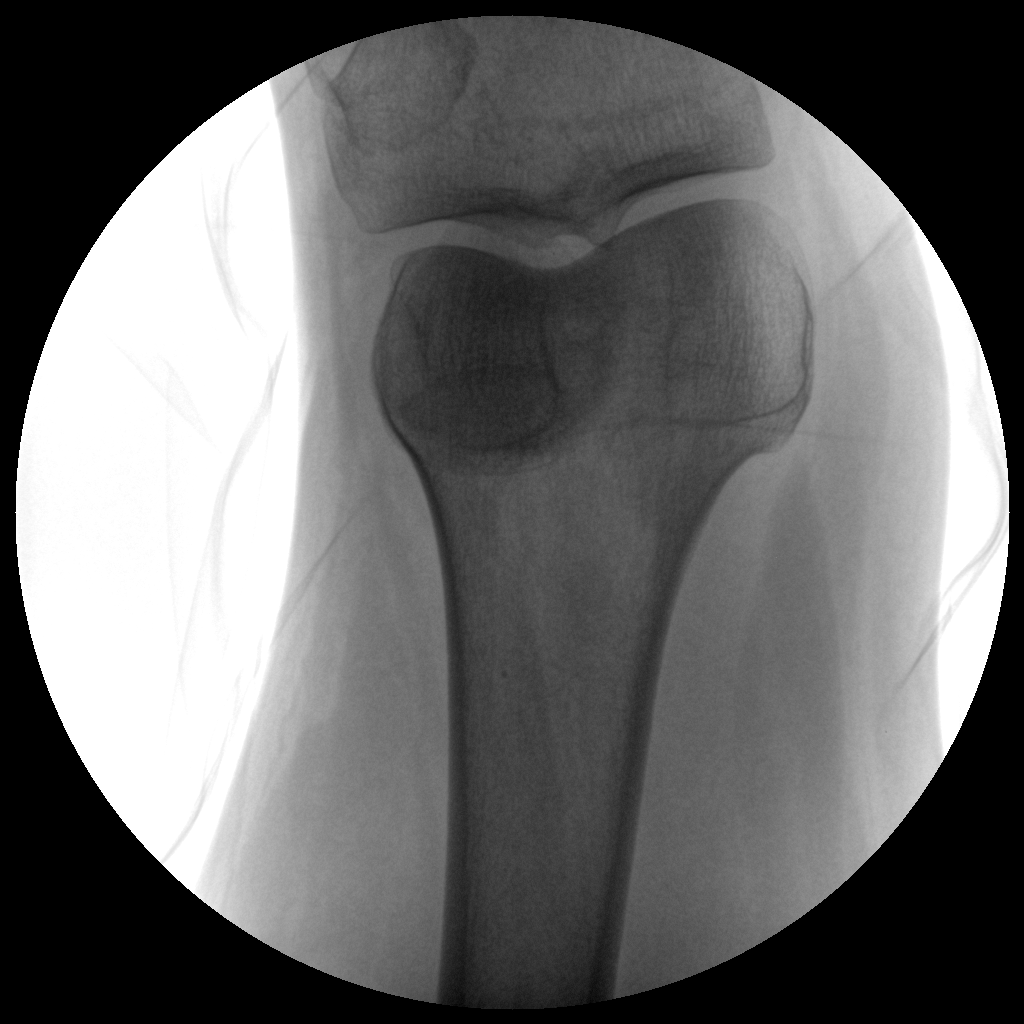

PLX112B 系列高频移动式手术X射线机

●经典影像工作站,可隔室操作避免辐射●全数字化百万像素影像系统,图像清晰●灵活的C臂机架设计,满足临床大范围运动●临床功能丰富,具备脉冲控制、数字摄影、自动透视等●具备手持控制器,远离主机也可自由控制